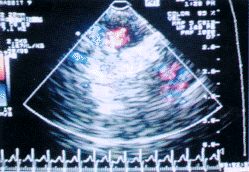

近场低回声区为眼眶,眼眶及脑组织内未见明显彩色血流信号

图1 造影前颅内彩色多普勒血流图

眼眶及脑组织内多处可见红兰伴行之彩色血流信号

图2 造影后颅内彩色多普勒血流图